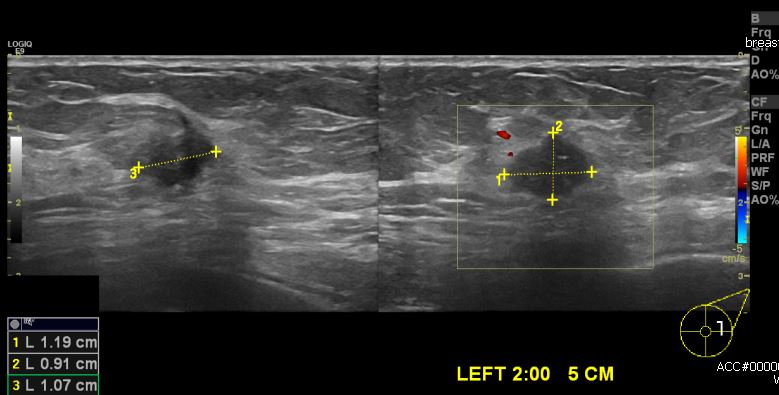

건강검진상 이상소견으로 내원하심 70대 여성분으로 좌측 2시 방향 5cm 떨어진 곳의 의심스러운 혹 중심핵생검 시행하여 좌측 침윤성 유관암 진단 되었습니다.